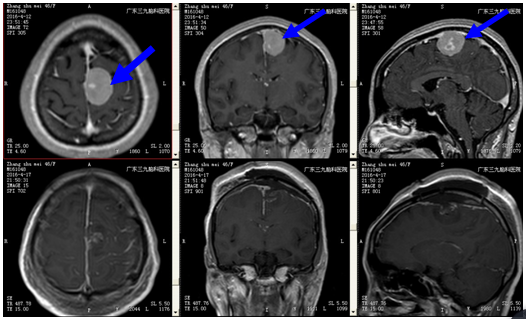

张女士,46岁,1月余前无明显诱因下出现头痛,呈阵发性,以左侧额部为主,可自行缓解,遂到当地医院诊疗,查头颅CT、MRI示:左侧额部镰旁占位性病变,考虑脑膜瘤可能性大。为求进一步治疗,来我院就诊,诊断:左侧额部镰旁脑膜瘤。入院后完善相关检查,未见明显手术禁忌症,全麻下行“左侧中央区镰旁脑膜瘤切除+ICP探头置入术”,术后予止血、脱水、抗感染、神经营养及补液等系统治疗后,康复好转出院。病理回报提示:脑膜瘤。

矢状窦、大脑镰是脑膜瘤的好发部位。根据文献报道在所有的脑膜瘤中分别占14.7%和8.7%。仅次于大脑凸面脑膜瘤.多呈球状生长并与矢状窦、大脑镰粘连。部分肿瘤可嵌人上矢状窦引起矢状窦部分或完全阻塞,而且瘤体大部分嵌于脑内,多向一侧生长,亦有双侧生长。位于矢状窦中1/3、后1/3者与运动区、视中枢及重要引流静脉的关系,使手术切除肿瘤存在较大的难度和风险。随着现代显微神经外科技术的发展。显微外科手术治疗矢状窦镰旁脑膜瘤的安全性和效果明显提高。病灶切除后,以癫痫发作为主要表现者术后均获良好效果。术前常规药物预防癫痫发作,使用高渗性脱水剂及皮质激素3~5d控制脑水肿。CT、MRI检查是诊断矢状窦镰旁脑膜瘤的最常用方法,能明确肿瘤的大小、位置与重要脑功能区的关系,利于设计手术切口,还需行MRV或DSA全面了解肿瘤的供血情况,充分了解上矢状窦受累后通畅程度和瘤周静脉的代偿情况,为术中保护重要血管及矢状窦提供帮助。肿瘤位于矢状窦中1/3者:行功能核磁共振明确锥体束与肿瘤的关系.以利术中保护。开颅出血的控制矢状窦镰旁脑膜瘤多为颈内、外系统双重供血,肿瘤血供十分丰富,局部板障静脉及脑膜静脉参与引流,而且肿瘤巨大,侵及上矢状窦,颅内高压可使引流静脉受压,颅内静脉血经板障静脉向颅外引流,开颅过程,在未能翻起骨瓣用骨蜡填塞板障止血时,出血常极为凶猛,甚至出现致命大出血。